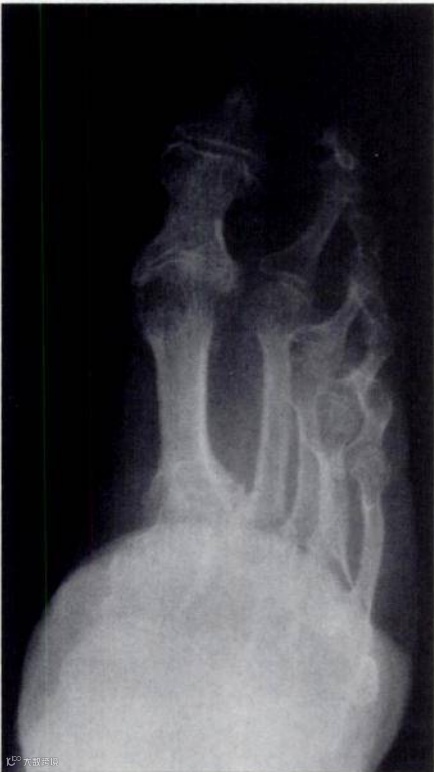

缠足是中国古代社会对女性身体的极端规训,不仅是一种文化现象,更是一种深刻的身体暴力。今天我们通过X线图像来窥探和审视这一古老习俗的残酷性,无声见证历史伤痕,隔空感受古代女性在成长过程中所承受的痛苦与压抑。

缠足的X线片显示外侧脚趾扭曲和足弓明显畸形。

(此图来源于香港医学科学博物馆,由香港放射科医生学院1996年捐赠)

X线影像让我们清晰地看到 “三寸金莲” 背后隐藏的残酷真相:足部骨骼的畸形、关节的退行性变以及足弓的彻底破坏、畸形,无一不是缠足这一习俗对女性身体造成的永久性伤害。这些影像不仅是医学的证据,更是历史的无声见证,提醒我们那段女性被迫承受痛苦与压抑的岁月。